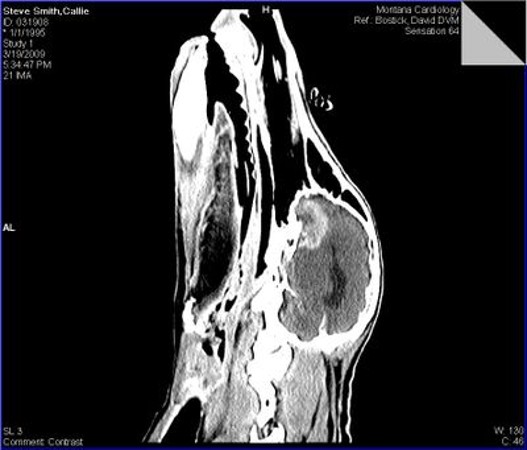

6

New cards

term image

CT scan - brain tumour